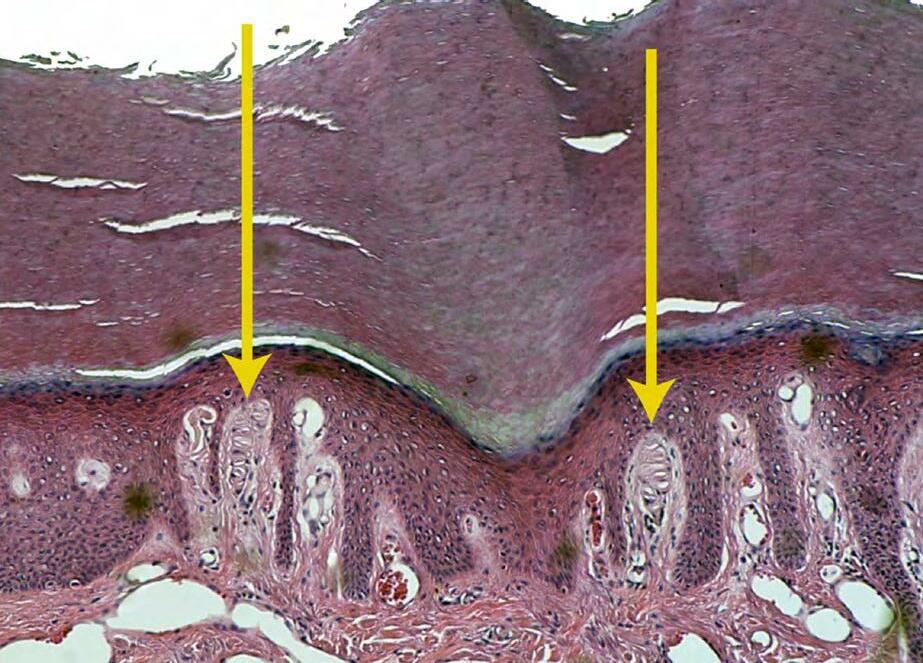

Just ask Joseph Ciano (D.O. ’16). As a medical student at NYITCOM, he worked with Brian Beatty, Ph.D., associate professor of anatomy, on a project that explored why some individuals are more sensitive to tactile sensations than others. Ciano analyzed skin tissue from the right hand of 16 cadavers under a microscope to document the number of Meissner’s corpuscles present in each finger, finger region (based on distance from the palm), and hand. That study, published in Annals of Anatomy in May 2022, suggests that variations in the distribution of Meissner’s corpuscles may explain why some people are more sensitive to tactile sensory cues—which could be advantageous for activities such as playing the piano, sculpting art, or performing osteopathic manual manipulation.

The project is one of many Beatty has engaged in with students to make use of cadaver remains after the completion of an anatomy course. Other projects included a study of oral mucosa, which Ciano also conducted, and current research on the surface metrology, or roughness, of skin assisted by Beatty’s “dermatology army” of students. “What we’re trying to do is develop techniques for studying people’s outsides to determine what’s happening on the inside without hurting them, such as making a model of a mole or keratosis on the skin to see if potentially we could develop this into a diagnostic tool for skin cancer.”

Brian Beatty’s research on Meissner’s corpuscles may explain why some individuals are more sensitive to tactile sensations than others. Top left, a histological image indicating Meissner’s corpuscles. Top right, a palm and finger view of the regions that were sampled.